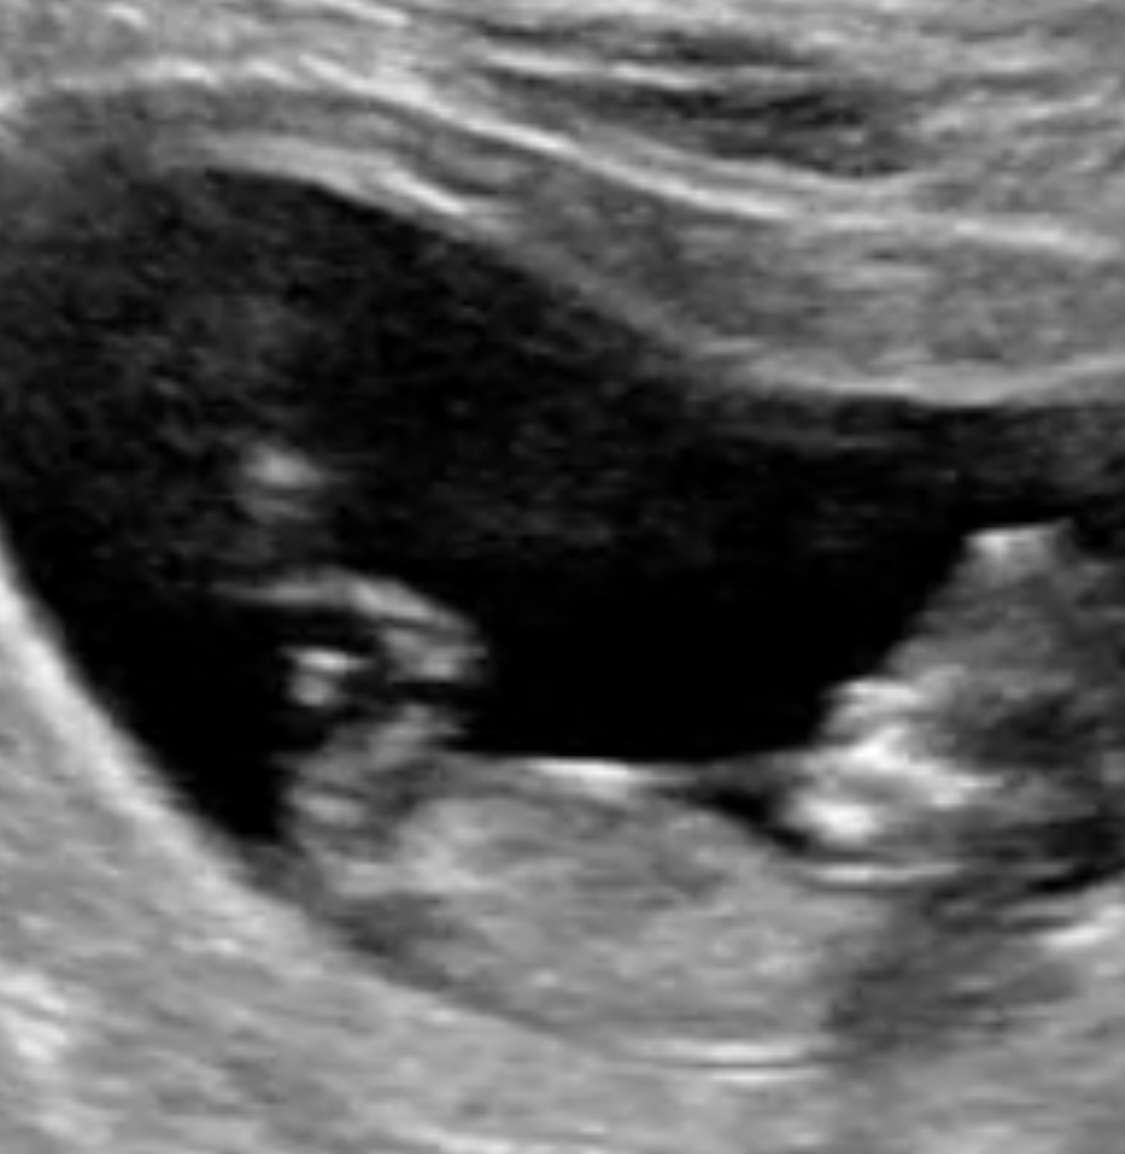

Gender Guess - 11 w 5 d scan

This is my 11 week 5 day scan! I’m wondering what the community thinks it will be! Boy or girl!?!?

My guess is girl